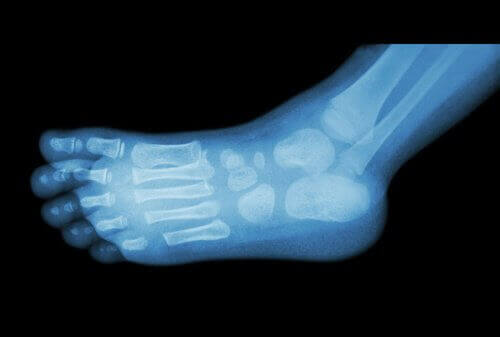

Leger bruker vanlig røntgen for å diagnostisere hælsporer.

Du kan vanligvis gjenkjenne en hælspore ved første øyekast, fordi de er små kuler som er forårsaket av en oppbygning av kalsium i hælen.